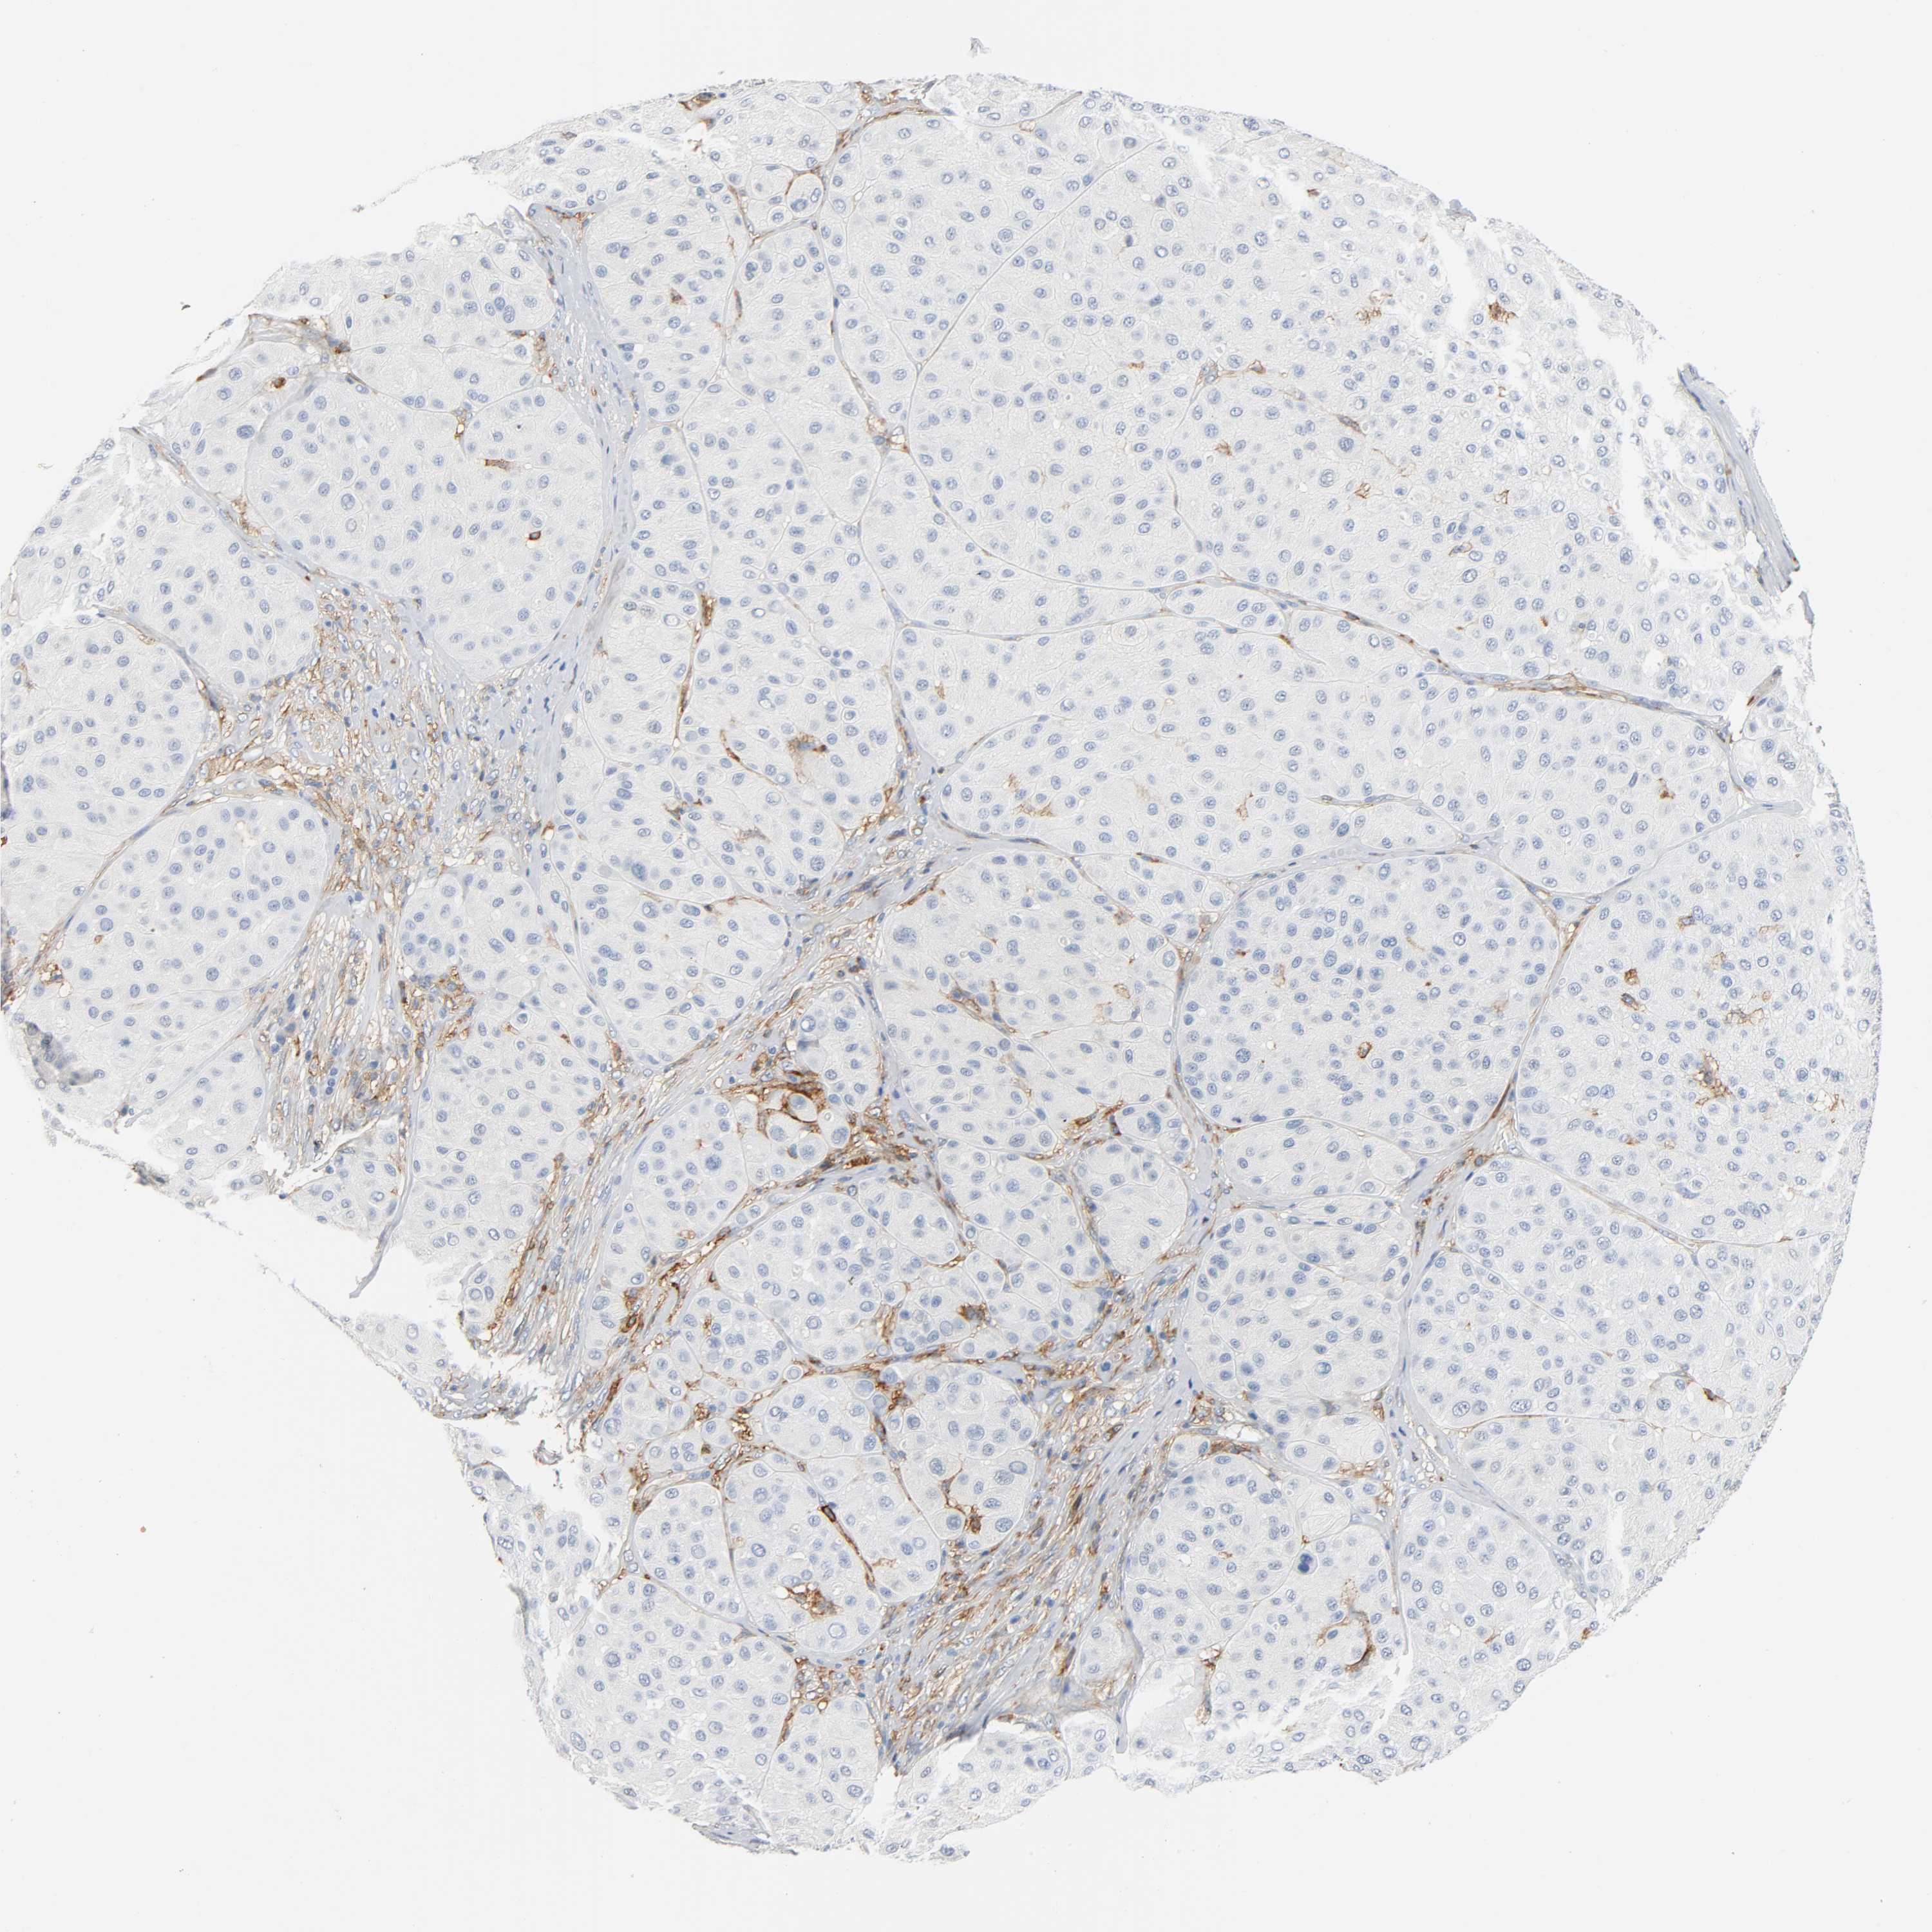

MELANOMA - Protein expressioni

A mouse-over function shows sample information and annotation data. Click on an image to view it in a full screen mode. Samples can be filtered based on level of antibody staining by selecting one or several of the following categories: high, medium, low and not detected. The assay and annotation is described here.

Note that samples used for immunohistochemistry by the Human Protein Atlas do not correspond to samples in the TCGA dataset.

Antibody stainingi

Antibody staining in the annotated cell types in the current human tissue is reported as not detected, low, medium, or high, based on conventional immunohistochemistry profiling in selected tissues. This score is based on the combination of the staining intensity and fraction of stained cells.

Each image is clickable and will lead to virtual microscopy that enables deeper exploration of all samples and also displays staining intensity scores, fraction scores and subcellular localization as well as patient and tissue information for each sample.

Antibody HPA004625

Antibody CAB002417

Staining

High

Medium

Low

Not detected

Intensity

Strong

Moderate

Weak

Negative

Quantity

>75%

75%-25%

<25%

None

Location

Nuclear

Cytoplasmic/membranous

Cytoplasmic/membranous,nuclear

Malignant melanoma, NOS

Malignant melanoma, Metastatic site